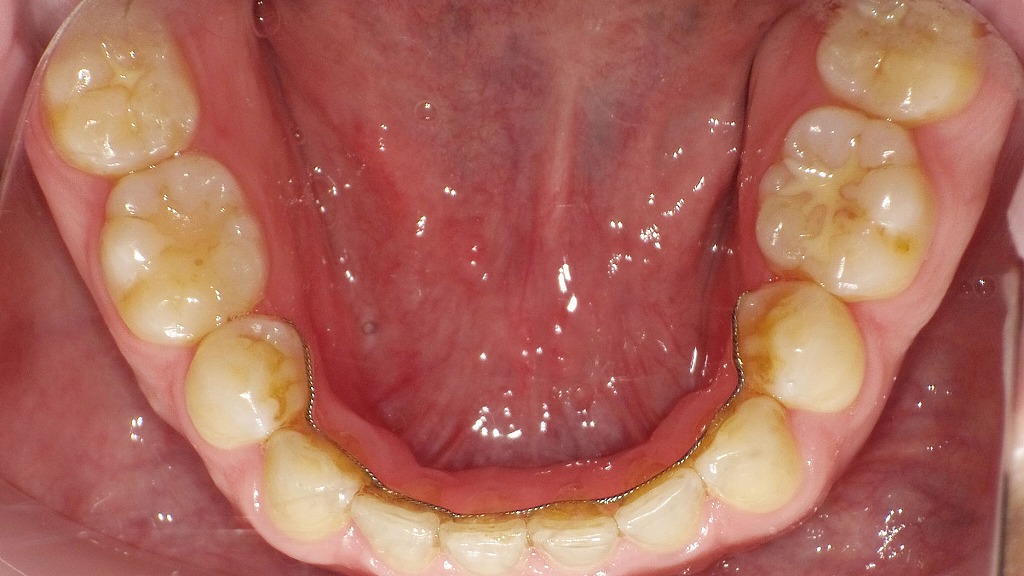

歯を動かしたあとは、何もしないと元の位置に戻ってしまう「後戻り」のリスクがあります。そのため、**保定装置(リテーナー)**を使って、整えた歯並びをしっかり安定させていきます。

リテーナーには、取り外し可能なマウスタイプと、歯の裏に固定するタイプがあります。保定期間中の装着時間は個人差がありますが、歯並びの安定にとって非常に重要な工程です。